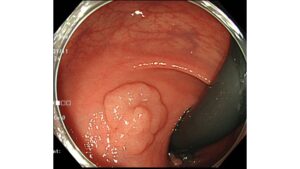

特殊光(NBI)による色差でみつける早期胃癌シリーズ②